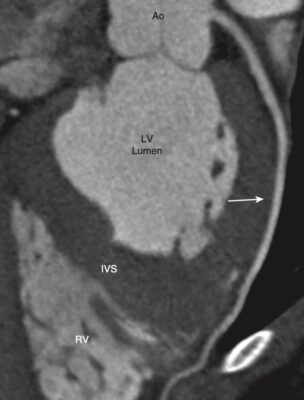

Mức tim thấp (Hình 10)

- Ở mức này, có thể xác định được nhĩ phải, thất phải, thất trái, màng ngoài tim và vách liên thất.

- Tâm nhĩ phải tiếp tục hình thành bờ tim phải. Tâm thất phải nằm ở phía trước, ngay sau xương ức, và thành xô xảm hơn thành tâm thất trái.. Tâm thất trái tạo ra bờ tim trái và bình thường có thành dày hơn tâm thất phải.

- Với thuốc cản quang tĩnh mạch, có thể nhìn thấy vách ngăn liên thất giữa tâm thất phải và trái.

- Màng ngoài tim (pericardium) bình thường dày khoảng 2 mm và thường được bao bọc bởi lớp mỡ trung thất bên ngoài màng tim và lớp mỡ thượng tâm mạc (epicardium) ở bề mặt bên trong của nó.